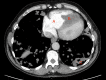

This case study is a rare example of cardiac hydatidosis in a high-income country, where a middle-aged man presented with a ruptured right ventricular cyst causing anaphylaxis, pulmonary emboli and dissemination of Echinococcus throughout the lung. He survived the cyst rupture and underwent cardiac surgery but had incomplete resection and experienced progressive cardiopulmonary hydatidosis despite antihelminthic therapy. As a result, he experienced an array of cardiopulmonary sequelae over his lifespan. This case report highlights rare clinical manifestations of hydatid disease and potential complications of its treatment.